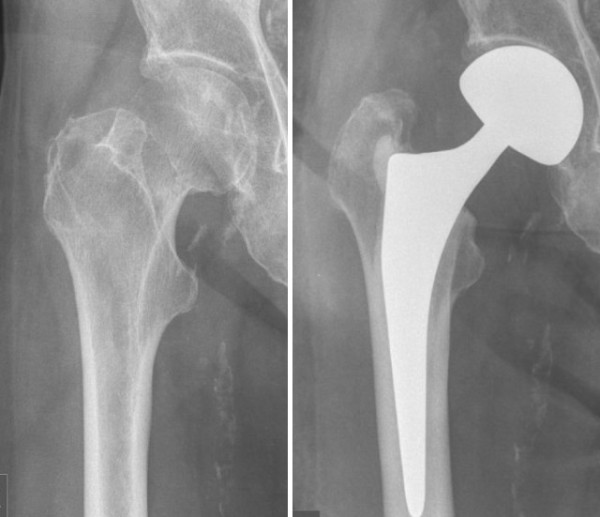

The company ORTHOPEDIC NIKIFOROV was founded in 1998 by the candidate of medical sciences. doctor of orthopedic-traumatologist of the highest category Nikiforov IA Owing to high professionalism and results of work, ORTONIC has gained well-deserved reputation and reputation among colleagues and population of Dnepropetrovsk region and CIS countries (Russia, Moldova, Armenia, etc.). The principle of the enterprise is NO IMPOSSIBLE, it is based on knowledge, experience and active implementation of modern technologies in orthopedics and traumatology. Conservative methods of treatment include individual selection of medicines, therapeutic blockades, manual therapy, massage, physiotherapy (vibration table, magnetotherapy, bioptron, electromyostimulation, etc.), rehabilitation with the suggestion of the necessary concomitant devices and means for the fastest recovery (corsets, bandages, various joint fixators, crutches, walking sticks, etc.). Various minor invasive interventions (chymonucleolysis, vertebroplasty, kyphoplasty, percutaneous nucleoplasty using cold plasma) that are performed on an outpatient basis are successfully used to treat problems associated with spine pathology. The latest modern treatment methods introduced in our company are endoscopic operations using the TYSSES technique of Joimax (Germany) with intervertebral hernias, stenosis and other pathologies of the spine, which allow to avoid complications occurring during open operations and the accompanying general anesthesia. We have many years of successful experience in traditional and modern minimally invasive endoprosthetics of large and small joints, which remains the main direction of our activity. Our company is the exclusive representative of the German company IO International Orthopaedics Holding GmbH, which based on the already known prostheses, its ideas and technological capabilities, has developed and implemented a new concept in hip replacement - an artificial joint prosthesis (ICON). We assist interested colleagues in training the operative technique for installing an artificial joint prosthesis - ICON, both in the workplace and in Germany. For 20 years we have been successfully cooperating with Sanitatshaus Gerd Klinz ortho team, an enterprise that for 20 years has been one of the leading places in Germany for the production of functional prostheses of the upper and lower limbs, as well as cosmetic prostheses of limbs and other body parts (nose, ears, eyeballs, fingers). We have an atmosphere of friendliness and human participation. Politeness, benevolence, the desire to understand and help is the basis of our attitude towards patients. We are always glad to see you and will do our best to make you feel great! We are waiting for you at: Ukraine, Dnepr, Gagarin Ave., 13 (under reconstruction) on all questions to address: tel .: +38 (050) 488-88-92 E-mail: orthonik.ukr@gmail.com Germany, Spine Nano Klinik, Zeppelinstr. 21, Potsdam Tel. +4901801121919 E-mail: kmw.nikiforov@hotmail.de